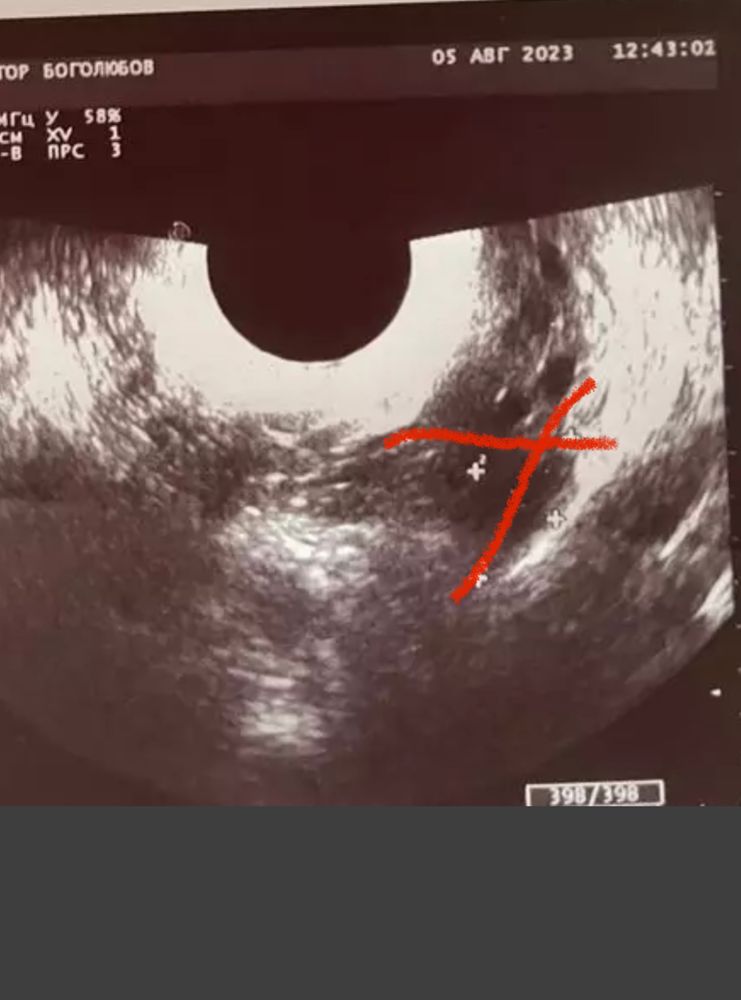

была на узи на 20 дц (так как с мужем ездили в отпуск, не могла сделать раньше) сказали что-то видят в правом и левом яичниках. Вроде как доминантные фолики, а вроде и желтое тело, или вообще «может это дырочки после дриллинга». Этот узист вызвал у меня недоверие, я пошла на сл. День в другую клинику и сделала узи там. Врач сказала, что не видит никаких ДФ и что овуляции вообще не было, и жидности в позадиматочном пространстве нет. Эндик всего 6мм. Узи подкрепляю. Третье фото это узи на 21дц. Подскажите пожалуйста, что это было?

Первый узист, похоже, принял два фолликула за один большой, разделила их на маленькие как мне кажется